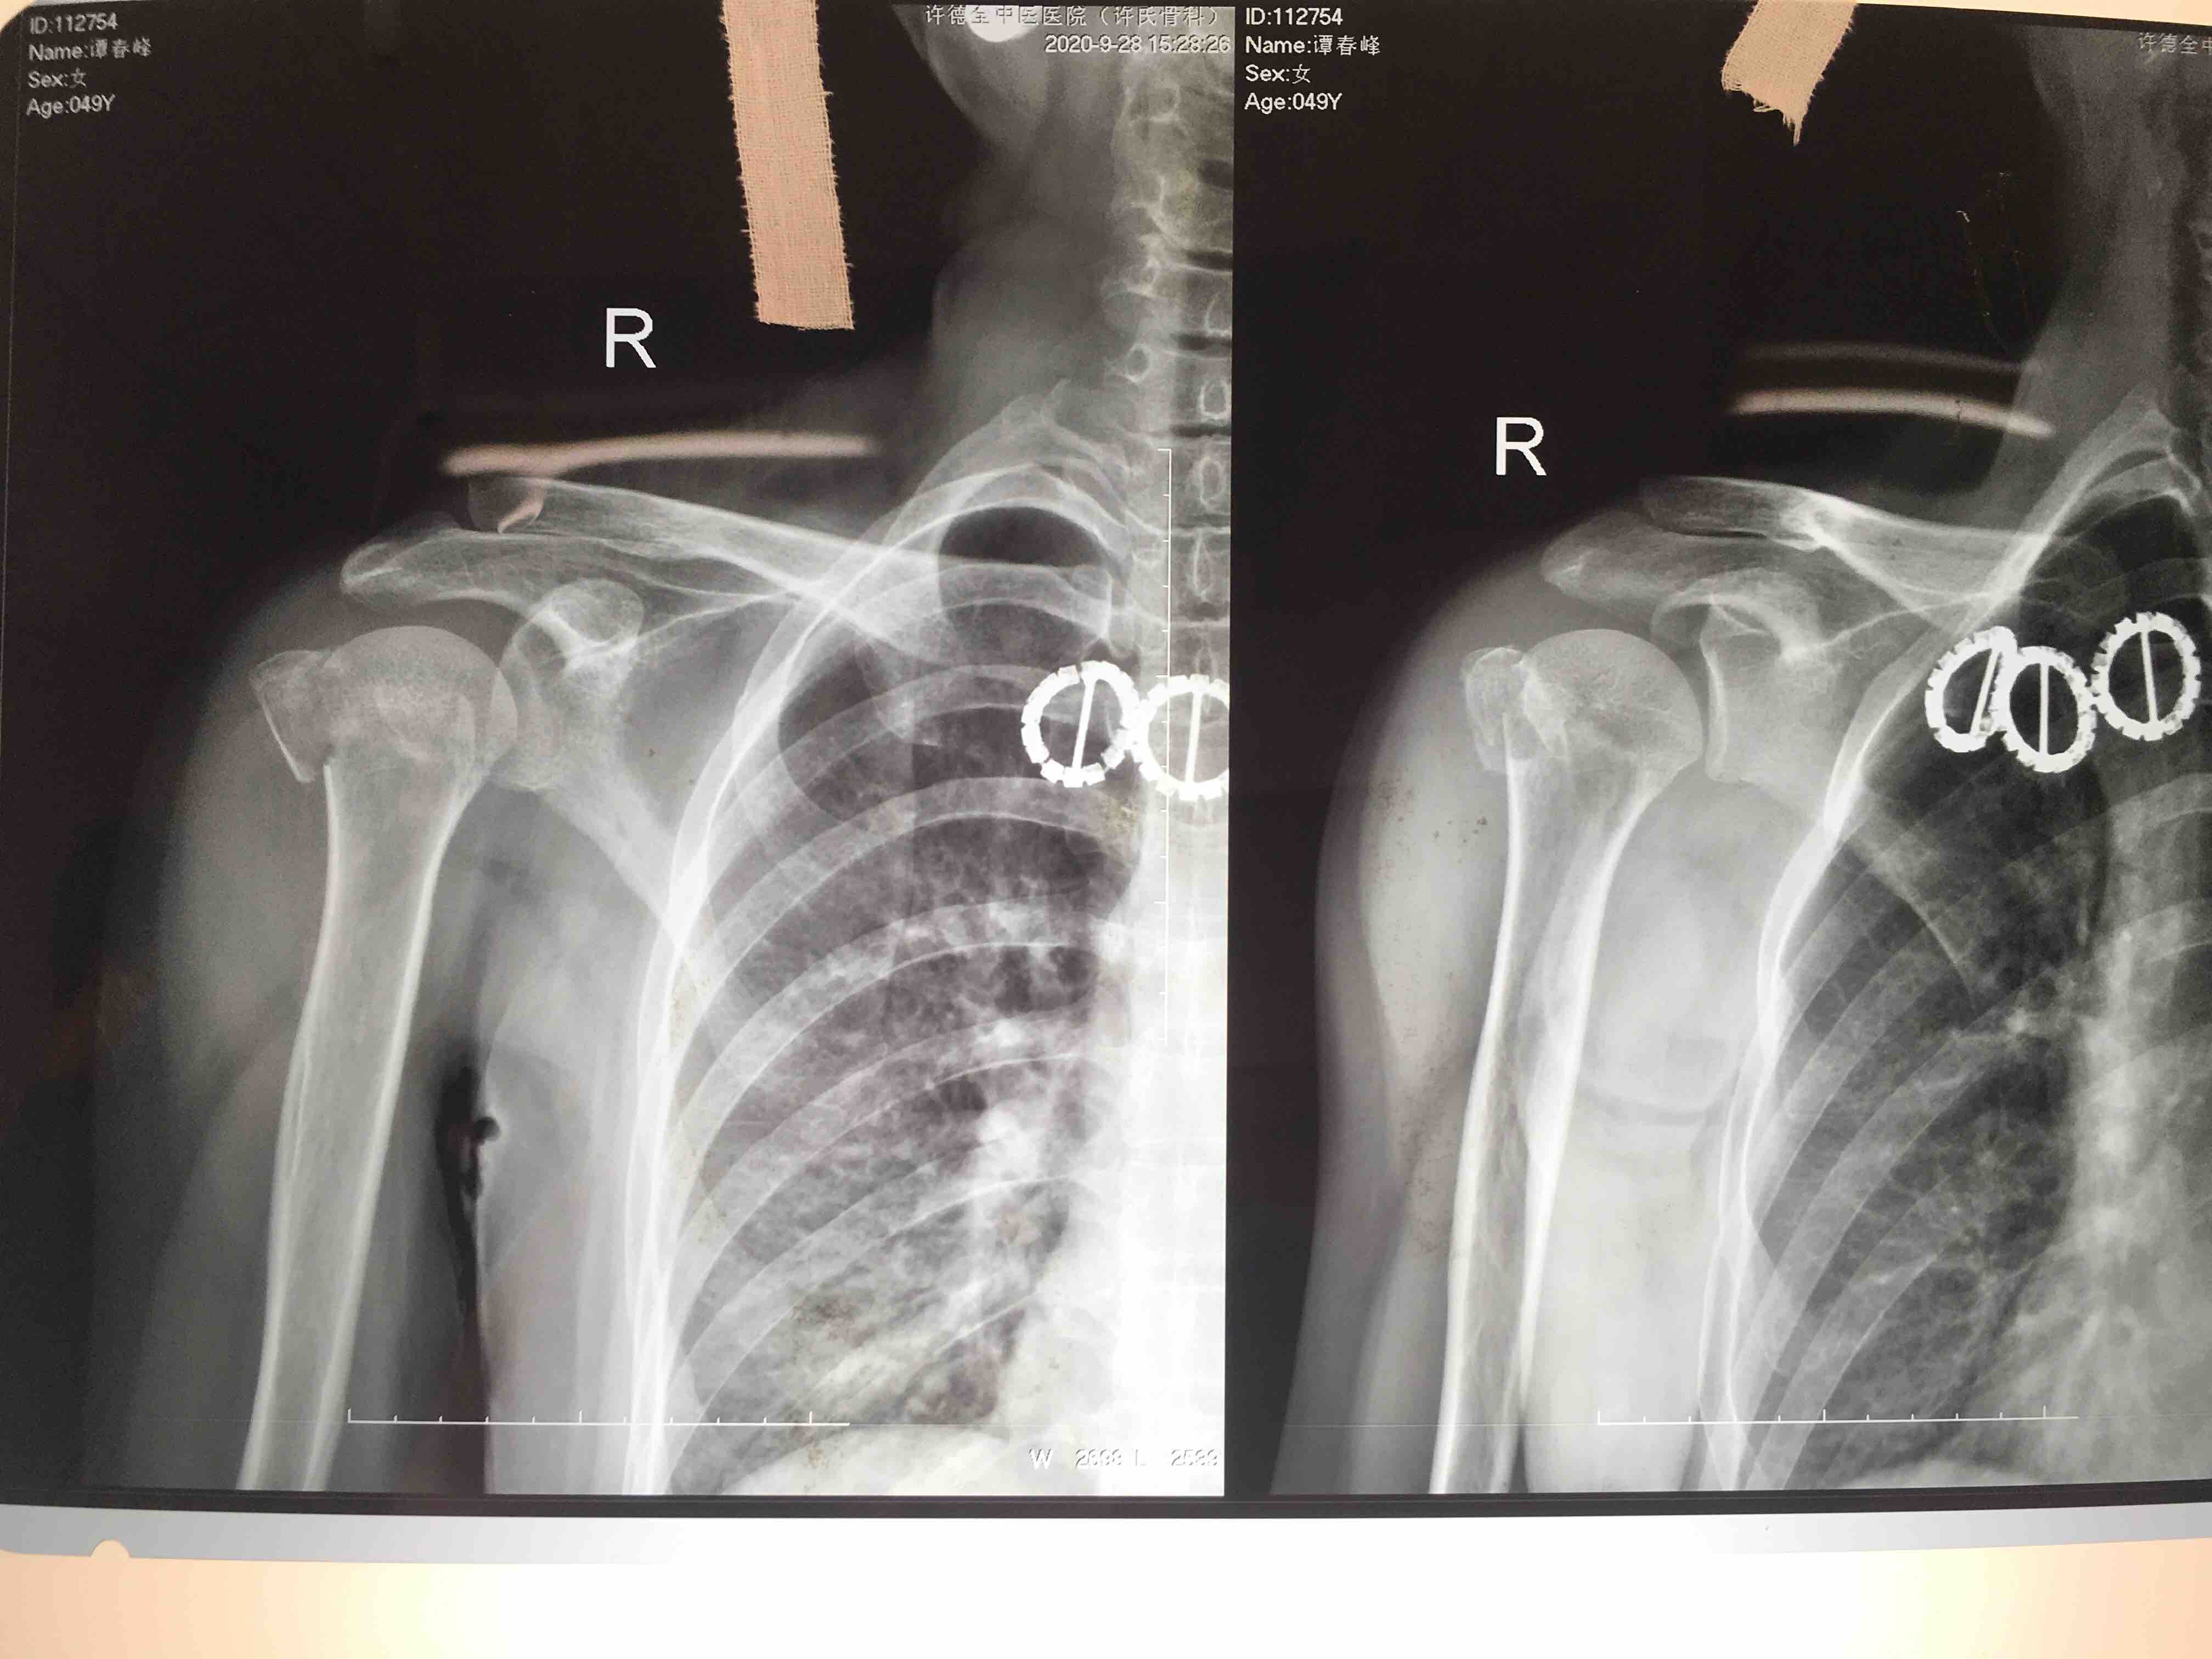

肱骨大结节骨折(切复内固定术)

摔伤后右肩疼痛不适1小时入院。既往身体健康,无其他不良嗜好。

右肩部肿胀,局部皮色皮温正常,压痛及叩痛阳性,活动受限,末梢血运感觉正常。

在臂丛麻醉下行切复内固定术,术后外展架固定4.一6周。